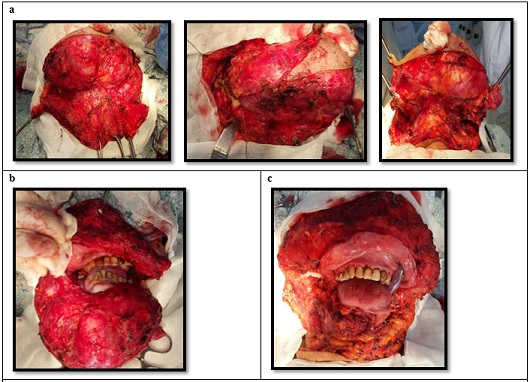

Given the massive involvement, the mandible was removed as a single block with the adjacent tissues (Figure 4a, 4b &4c).

a – stages of tumor exposure; b – dissected tumor; c – surgical defect after subtotal resection of the mandible. Figure 4: a – stages of tumor exposure; b – dissected tumor; c – surgical defect after subtotal resection of the mandible.

On March 2, 2016, the patient underwent Stage I surgery: subtotal resection of the mandible with reconstruction of the oral defect using local tissues. The surgical approach was achieved by excising a skin-subcutaneous flap 22 cm in length from the right ear to the angle of the left side of the mandible (Figure 3). The tumor involved the right half of the mandible up to its ramus and extended to the left angle, causing destruction of the bone tissue.

The mandibular defect was repaired with local tissues, ensuring a watertight seal of the mucous membrane (Figure 5).

Condition after reconstruction of the postoperative bed with local tissues. Figure 5: Condition after reconstruction of the postoperative bed with local tissues.